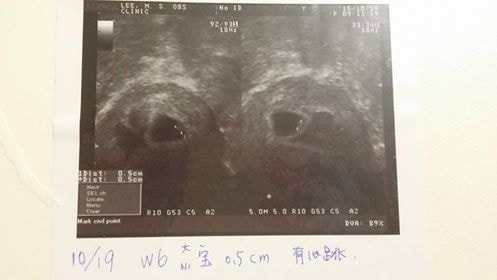

今天回診看寶寶,距離上次才四天的時間而已,三個寶寶的小手,小腳都已經長出來囉!真的是超級可愛的。

三個寶寶很健康,從頭,心臟,手跟腳,身高,都很正常。